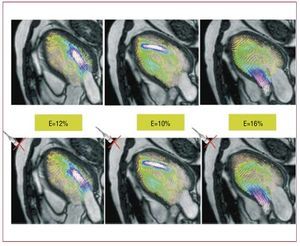

We recently introduced a new noninvasive modality to measure 2D flow fields in the apical long-axis view of the LV using conventional color-Doppler ultrasound.161-163 Such flow fields can be overlaid on anatomical images, allowing visual and quantitative characterization of LV flow features with high temporal resolution. The clinical simplicity of this modality enables the hemodynamics of the LV diastolic vortex to be studied in large numbers of cases. The normal velocity component in the ultrasound beams is estimated from the mass-conservation equation, which is simplified based on the assumption that the flow is approximately 2D in the plane of interest due to the elongated shape of the mitral inlet. Integrating the mass-conservation equation from the anterior wall and from the posterior wall separately, and then combining the 2 integrals, reduces the error associated with the 2D simplification. Laser PIV experiments performed on an atrio-ventricular duplicator209,210 supported the 2D simplification in the apical long-axis view of the LV for different interrogation positions of the Doppler sector.161,162 Although further work is needed to test the 2D-flow hypothesis in vivo, its validity is supported by existing PCMR measurements,211 as well as by our own preliminary PCMR data from healthy and diseased LVs (Figure 13). In the cases studied so far (N=3), the relative error of the estimation ranges between 10% and 20%, and has no systematic dependence on the phase of the cardiac cycle.

Figure 13. Vector maps of blood flow in the apical 3-chamber view of a human left ventricle, showing original phase-contrast magnetic resonance measurements (top row) versus data estimated from the continuity equation for a virtual transducer in locations indicated by the red crosses (bottom row). The green boxes indicate the root mean square error of the estimation, E. Each column shows a different time instant during the cardiac cycle. Adapted from García et al.162